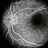

- No history. Fluorescein angiogram of the left eye showing no leakage in the macular area.